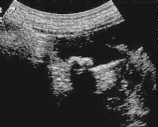

腹部エコー検査

エコー検査は超音波を使った検査でお腹にゼリーを塗って検査します。胆石の数や種類、胆嚢壁の異常など得られる情報が多く、手軽に何回も繰り返して検査することができます。左のエコー写真には1個、右の写真には2個胆石が写っています。